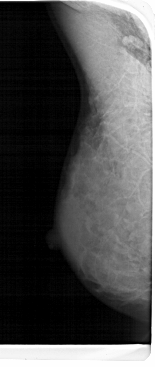

A_1482_1.LEFT_MLO

LEFT_MLO LINES 5491 PIXELS_PER_LINE 2311 BITS_PER_PIXEL 12 RESOLUTION 43.5 NON_OVERLAY